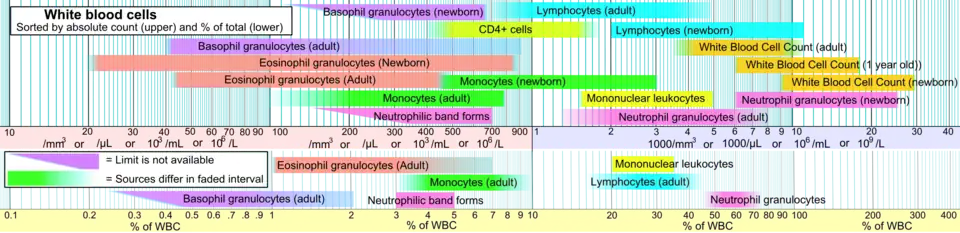

Neutrophils are a type of phagocytic white blood cell and part of innate immunity. More specifically, they form the most abundant type of granulocytes and make up 40% to 70% of all white blood cells in humans.[1] Their functions vary in different animals.[2] They are also known as neutrocytes, heterophils or polymorphonuclear leukocytes[3].

Neutrophils are the most abundant white blood cells in the human body (approximately 1011 are produced daily); they account for approximately 50–70% of all white blood cells (leukocytes). The stated normal range for human blood counts varies between laboratories, but a neutrophil count of 2.5–7.5 × 109/L is a standard normal range. People of African and Middle Eastern descent may have lower counts, which are still normal.[18] A report may divide neutrophils into segmented neutrophils and bands.